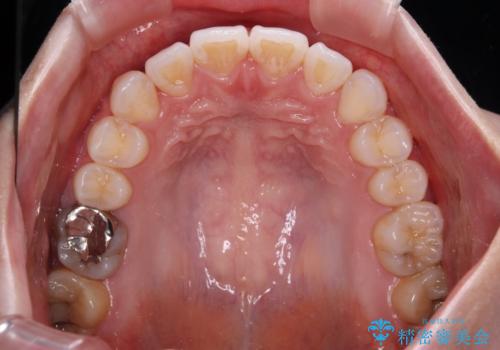

- 左右の八重歯を気にして来院された患者様です。

歯列としてはインビザラインでもワイヤー矯正でも対応できるものでしたが、インビザラインによる治療を希望されていました。

上顎の八重歯改善にインビザラインでは時間のかかってしまう可能性があり、更には口元が治療前よりも突出してしまう可能性があったため、補助装置により八重歯を事前に引き込んでおくことで、インビザラインによる治療をスムーズに行えるように計画しました。

補助装置を使用したことで、口元が突出することもなく、スムーズに仕上げることができました。